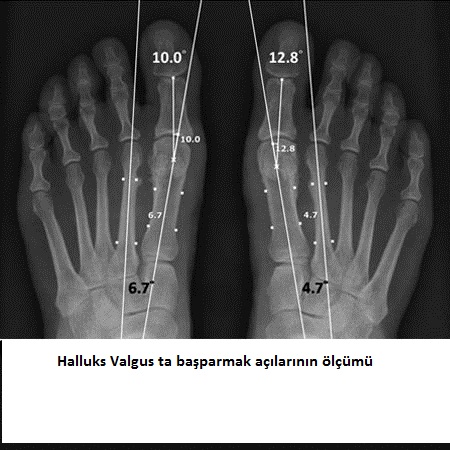

Bir başka Halluks Valgus şiddetini derecelendirme yöntemi intermetatarsal açı (IMA)’dır. Ölçüt birinci ve ikinci metatarsal kemiklerin uzunlamasına eksenleri arasındaki açıdır ve bu normalde 9 dereceden küçüktür. Metatarslar, ayak parmakları ve ayak bileği arasındaki ayak tarak kemikleridir.

halluks valgus dereceleri